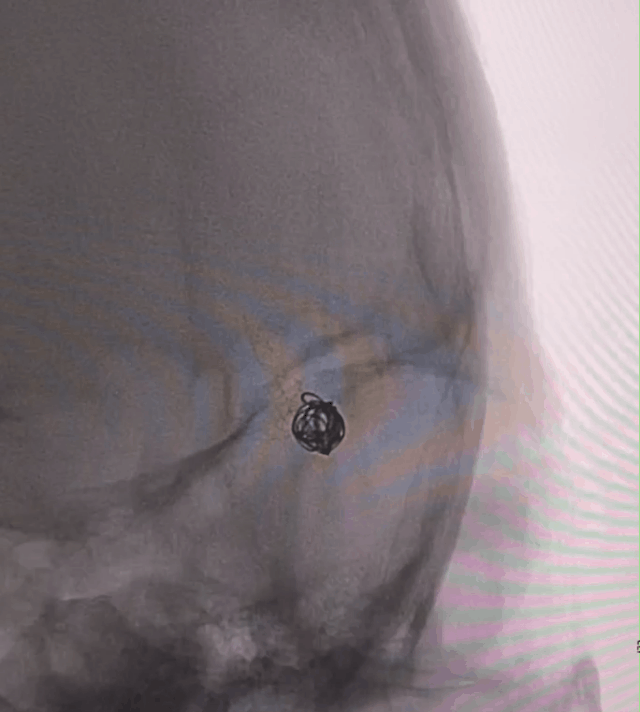

术后即刻造影提示载瘤动脉通畅,支架打开充分,贴壁良好,瘤体内造影剂滞留明显。

术后正侧位造影片提示颅内血管显影良好,支架打开充分,瘤颈处推密,贴壁良好,动脉瘤内造影剂滞留明显。